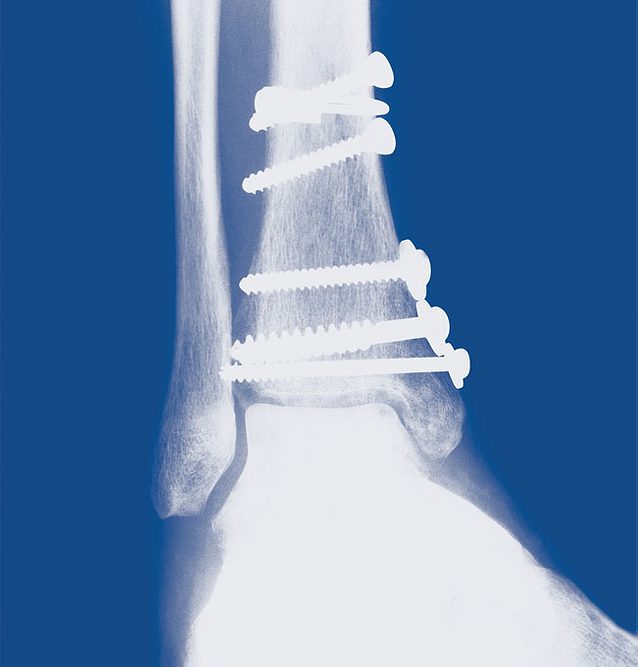

AN INSIDE LOOK. The screws and wire wrapping shown in this X-ray held Mike Ehlert’s bones together while his leg healed. The hardware remains in the leg.

The tibia, the larger of the two bones, suffered a long, vertical crack running down into the ankle. The fibula was broken not far below the knee. Doctors inserted five pins and screws, plus a wire wrapping, to piece the bones back together. The meter was running, well on its way to $22,000 in medical bills. Ehlert wouldn’t work again for 6 months, and only part time for 2 months after that.